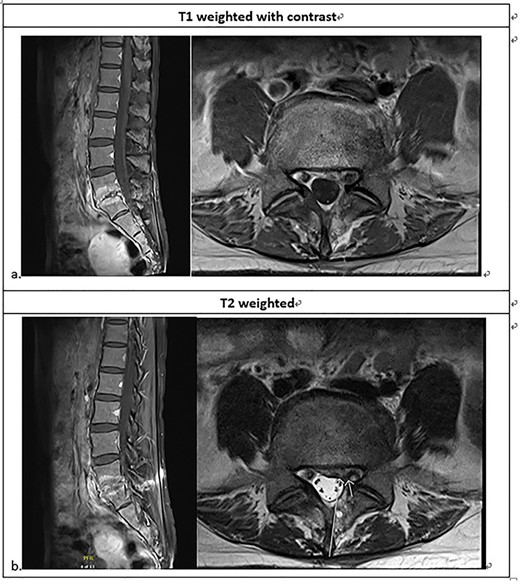

Lumbarsacral spine MRI (a) posterior bulging disc at L5-S1; extruding disc at the left subarticular zone of the left L5-S1, with compression of the left S1 nerve root; neural foraminal stenosis at left L5-S1; increased enhancement at L5-S1 related to the spondylitis change; (b) The arrow point at neural foraminal stenosis at left L5-S1.

She was referred to our institute for spine consultation at 3 months after surgery. On physical examination, she had numbness at the left S1 dermatome and saddle anesthesia. Visual analog scale was 8 when admission. The straight leg raising test was bilaterally negative. She had no lower extremity weakness. Contrast-enhanced lumbar-spine MRI showed posterior bulging disc with decreased disc space and endplate changes of L5-S1. We suspected an extruding disc in the left subarticular zone at left L5-S1, compressing the left S1 nerve root. There was increased enhancement at L5-S1, but the paraspinal soft tissue was clear without enhancement (Fig. 1).